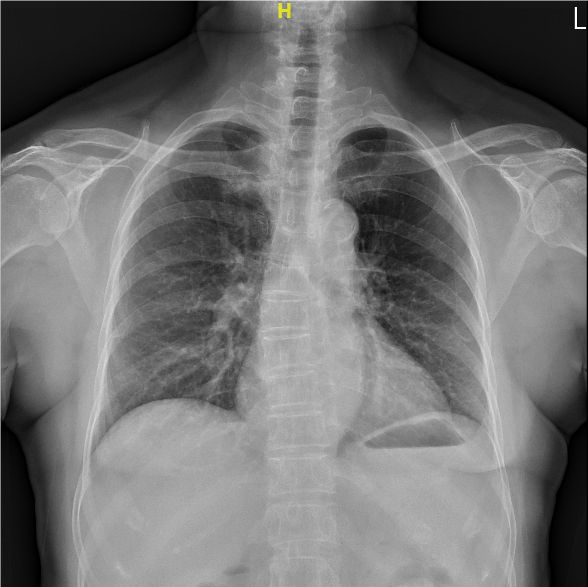

Kuang Tien’s Thoracic Surgery Department has treated countless patients in

the Central West Coast of Taiwan since its establishment in 1986. The

department is experienced in diagnosing and treating diseases in the

respiratory tract, lungs, pleura, and esophagus. The department continuously

improves its equipment in order to provide the best care possible.